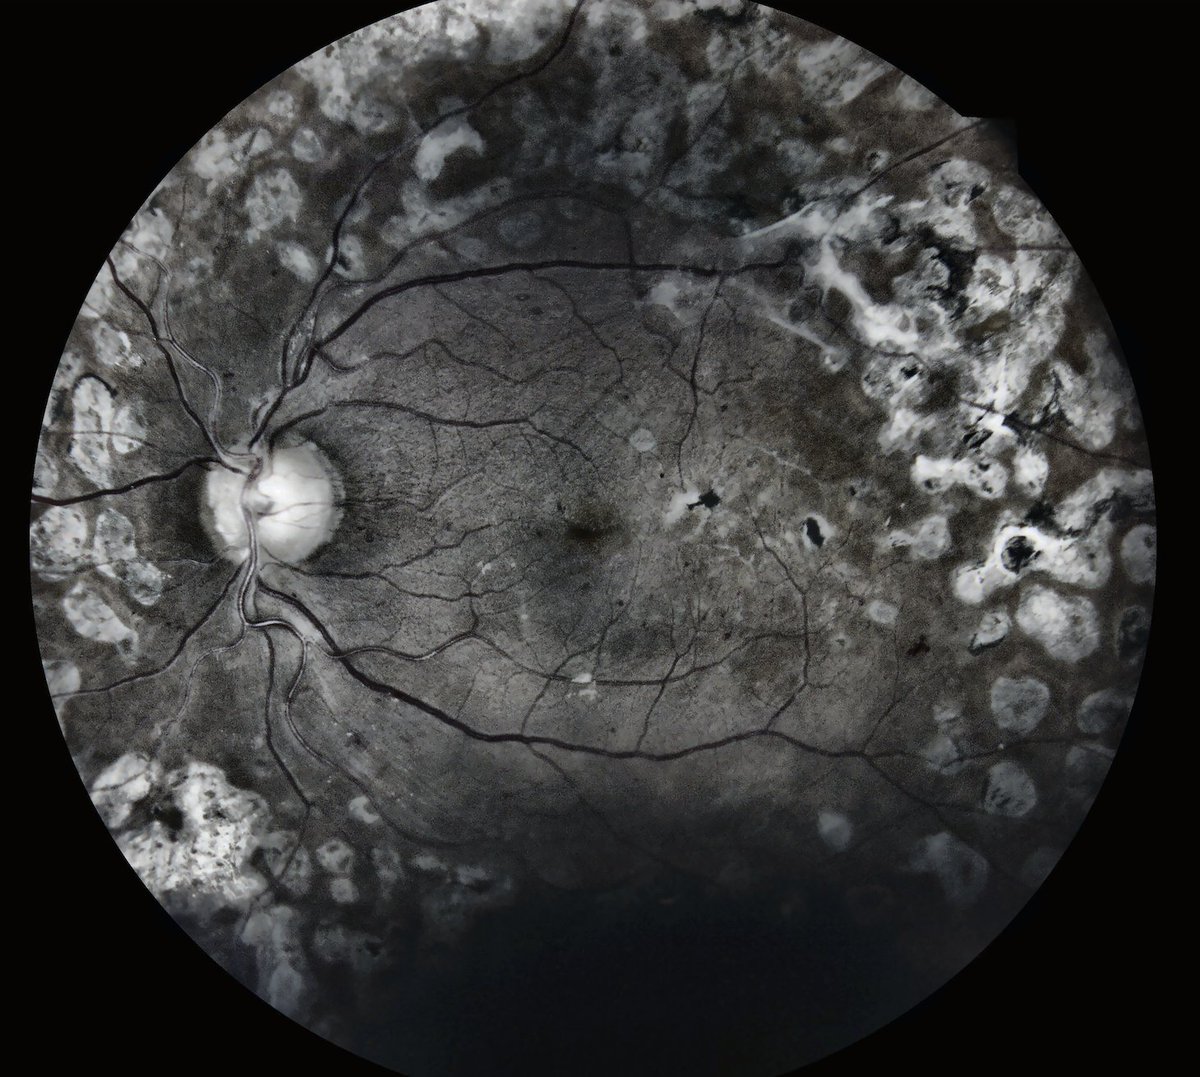

"The enhanced image does a great job of uncovering the possibility of #lipid underneath the dark shadow. The IRIS platform really does make the photos more #gradable." Jose Agustin Martinez, MD Keep reading about IRIS Image Enhancement Software ↓ retinalscreenings.com/blog/the-iris-…

IRIStelemed's tweet image. "The enhanced image does a great job of uncovering the possibility of #lipid underneath the dark shadow. The IRIS platform really does make the photos more #gradable." Jose Agustin Martinez, MD

Keep reading about IRIS Image Enhancement Software ↓

retinalscreenings.com/blog/the-iris-…